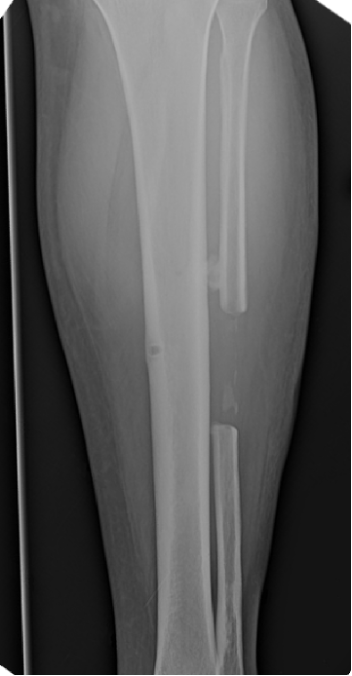

Under fluoroscopy, we then created a longitudinal incision over the central fibula, eight cm proximal to the ankle joint, to help prevent syndesmotic instability. A sagittal saw then helped harvest fibula graft to fit the previously measured deficit. After prepping the distal and proximal aspect of the remaining neck and base of the second metatarsal, the fibular graft was pressed and fitted into the defect. Once confirmed that the graft was the appropriate length to fit the deficit, we brought the graft to the back table, where we fixated a Y-plate to the graft to allow for ease of placement and fixation of the graft to the remaining bone fragments. At seven months postop, the patient ambulated in regular shoe gear with no complaints of foot pain.

Complications of harvesting the fibular graft include injuries to the peroneal nerve, compartment syndrome, local muscular problems, and ankle instability.9 Reports of complications for fibular grafts vary between four and 12 percent.5,10 Reports of problems in the ankle after harvesting a fibular graft range between 10 and 40 percent.11,12 Clinical studies have suggested that preserving the distal six to eight cm and the anterior syndesmosis can maintain lateral stability of the ankle.12,13 However, Pacelli showed that only 10 percent of the fibula was needed distally to maintain ankle stability, suggesting that maintenance of ankle stability can is possible with even less residual fibular length. In conclusion, as demonstrated in this case study, fibular grafts are effective and successful in reconstructing bone defects following traumatic injuries.